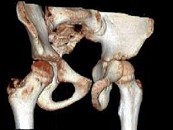

- 单项选择题男,13岁, 右髋部疼痛不适,无红肿, 结合所提供的图像,最可能的诊断是 ( )

E、骨纤维结构不良